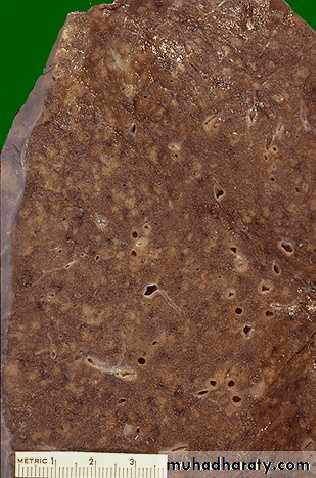

When the immune response is poor or is overwhelmed by an extensive infection, then it is possible to see the gross pattern of granulomatous disease seen here. This is a "miliary" pattern of granulomas because there are a multitude of small tan granulomas, about 2 to 4 mm in size, scattered throughout the lung parenchyma.